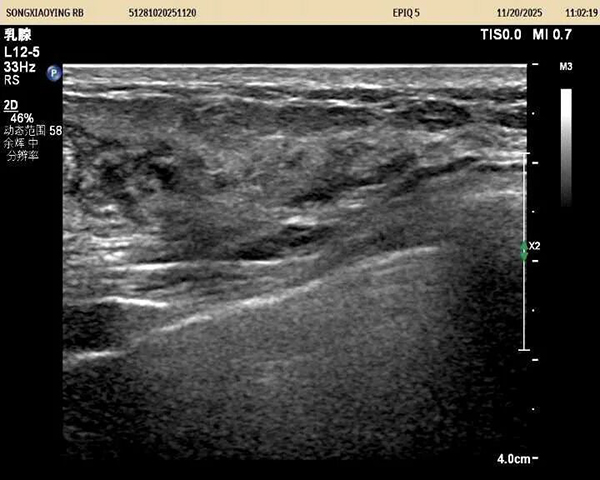

据悉,该患者三个月前自查发现左侧乳房有一质硬肿块,虽无红肿热痛等典型症状,但因担忧恶性病变而长期处于焦虑状态。就诊后,超声医学科主任王金萍迅速为其安排检查。超声影像显示:左乳3点位存在一大小约3.6×2.3厘米的混合回声包块。凭借丰富的临床经验,王金萍判断该病变为良性液性病灶,具备明确干预指征且无恶性风险。

在充分沟通并取得患者同意后,王金萍为患者实施了超声实时动态引导下的穿刺抽液术。术中精准定位病灶,顺利抽出白色糊状液体,并辅以生理盐水灌洗,使包块基本消失。整个过程患者无任何不适,术后即刻离院,情绪明显改善。后续病理结果证实:未见癌细胞,进一步打消了患者的顾虑。